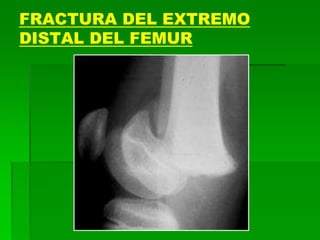

FRACTURA DEL EXTREMO

DISTAL DEL FEMUR